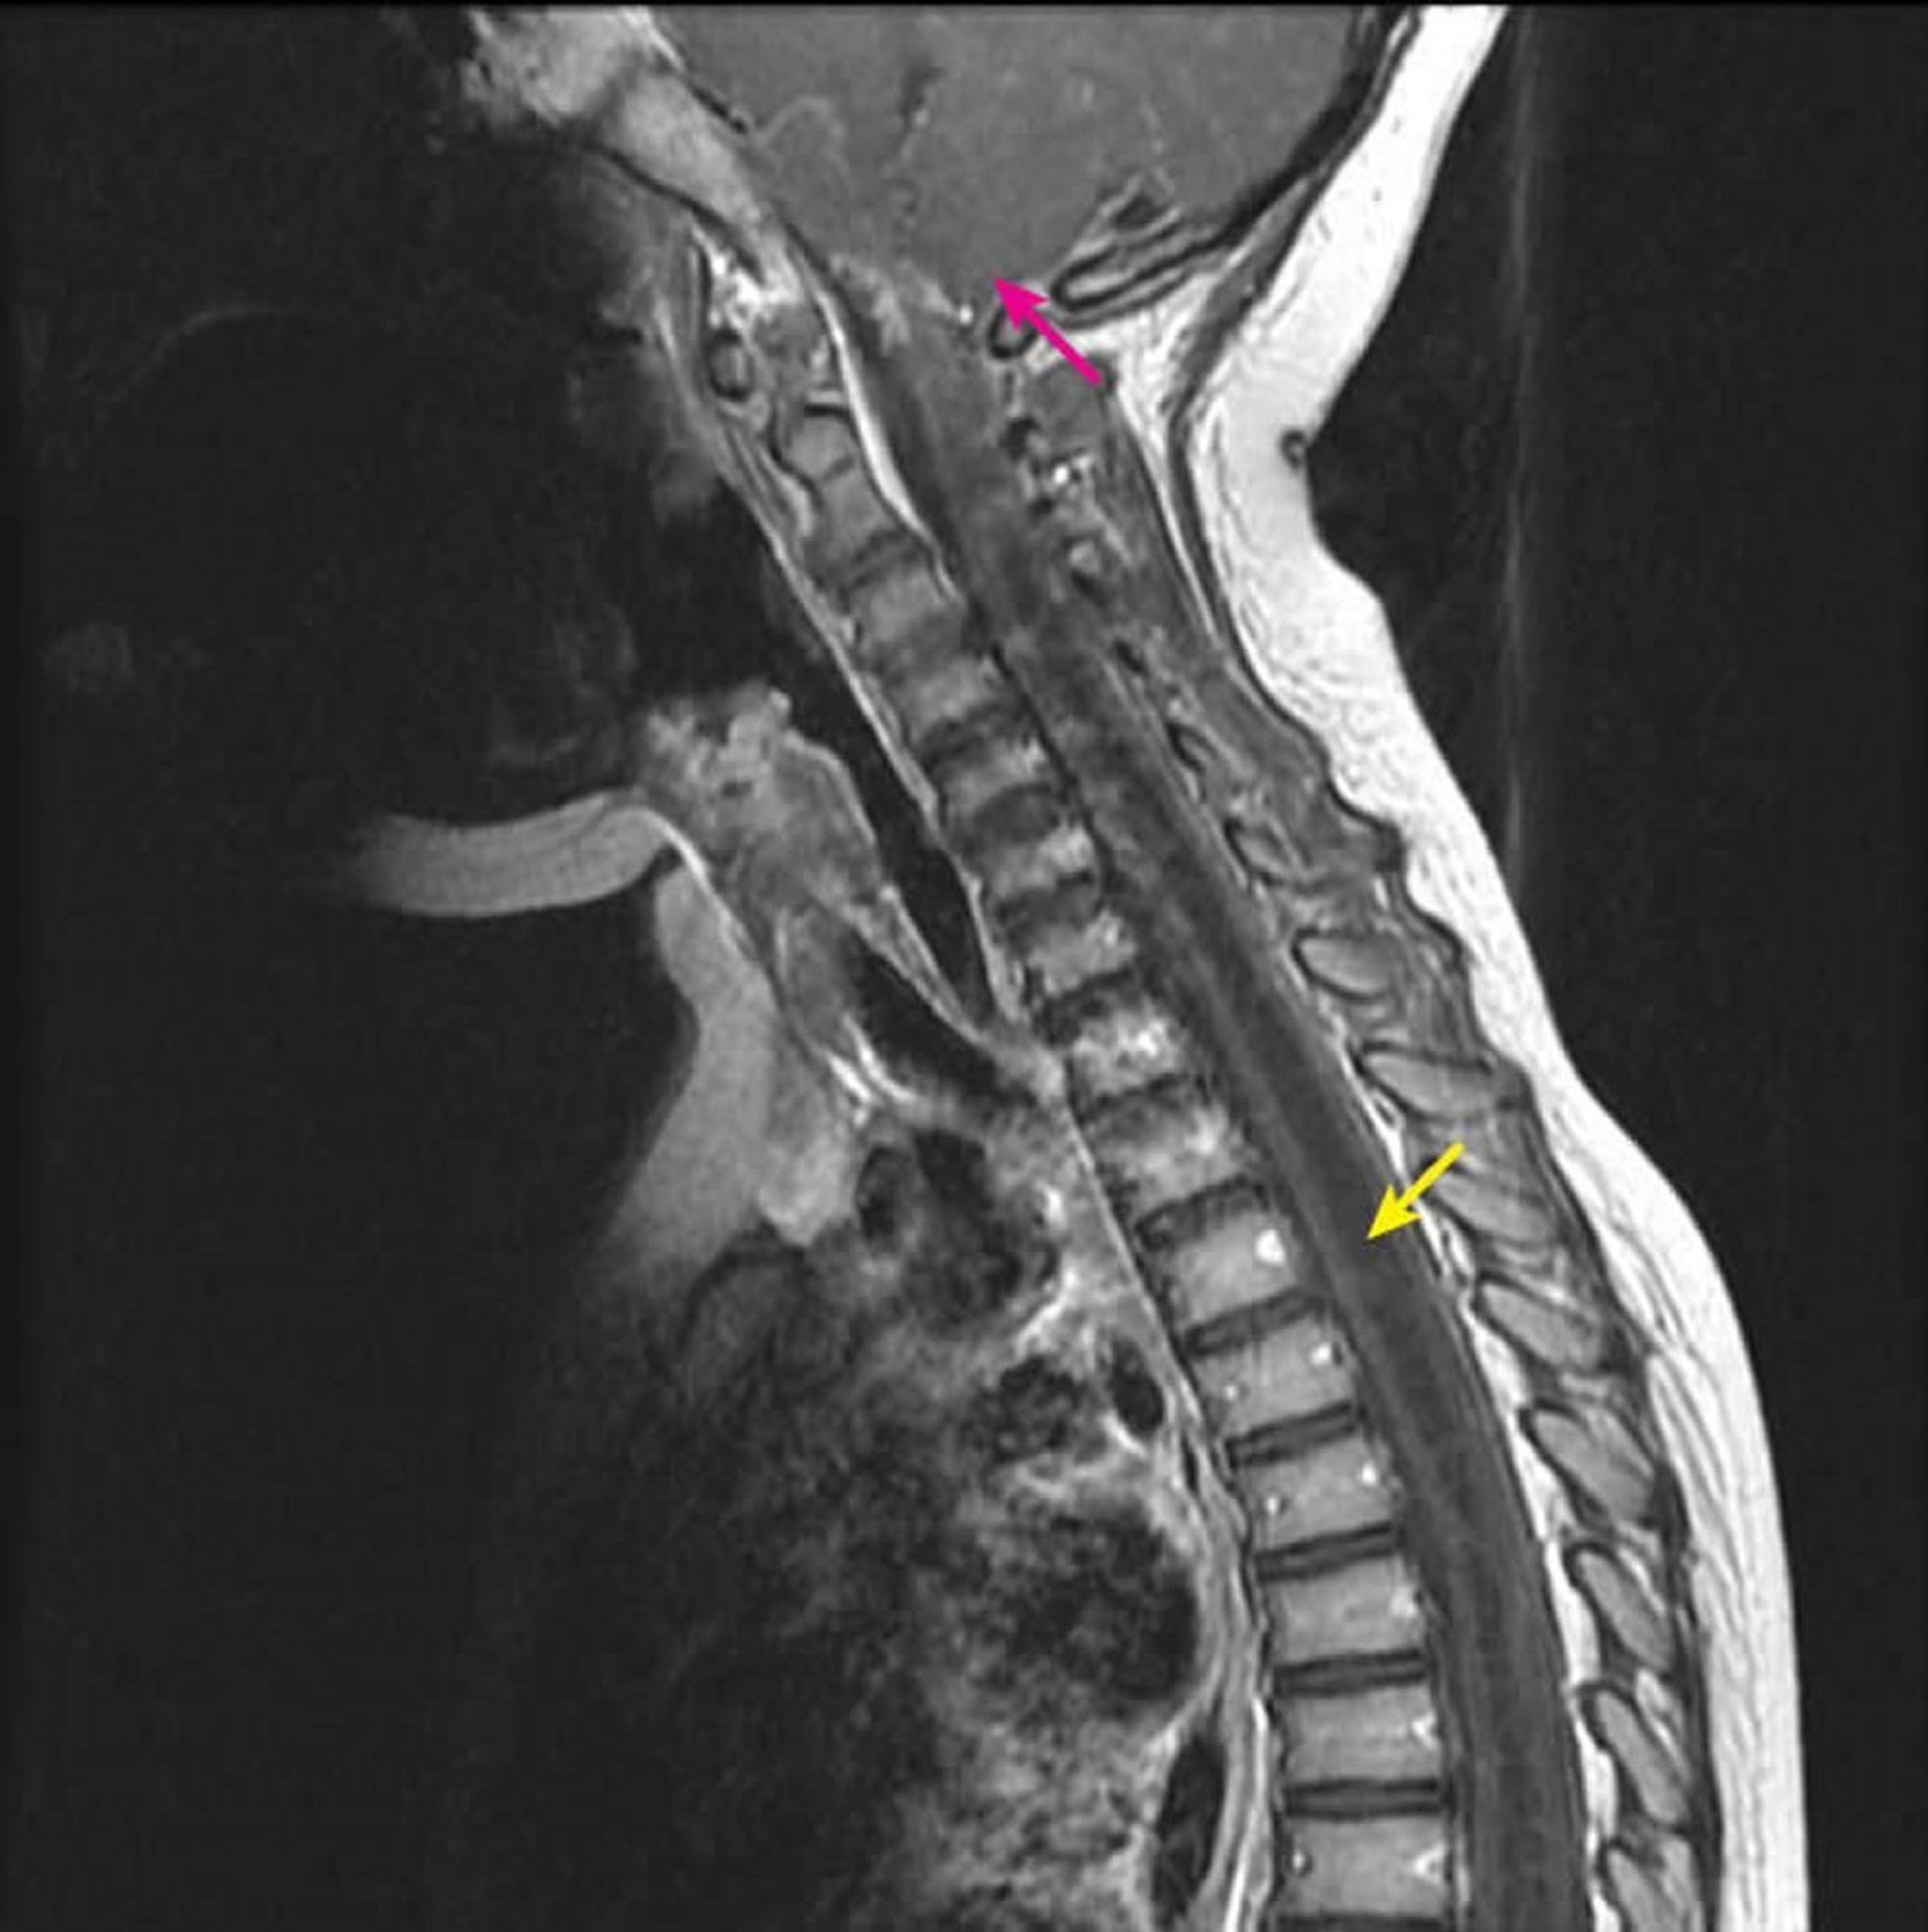

Cervicothoracic Syringohydromyelia

Sagittal post-contrast T1-weighted MRI shows a large T1 hypointense intramedullary spinal cord cavity characteristic of a syrinx (yellow arrow). It extends from the C2-3 cervical level inferiorly in a child with a known Chiari I malformation (pink arrow). This finding is defined as syringohydromyelia because syringomyelia (an eccentric spinal cord cavity) cannot be differentiated from hydromyelia (a central spinal cord cavity) by imaging.

Courtesy of John Tsiouris, MD, Division of Neuroradiology, New York–Presbyterian Hospital/Weill Cornell Medical Center.